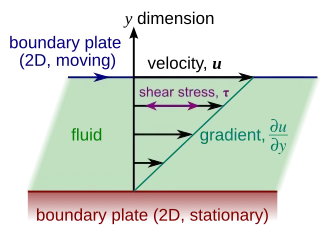

Stress

When force is applied to a material it starts to deform or move. As the force needed to deform a material (e.g. to make a fluid flow) increases with the size of the surface of the material A.,[6] the magnitude of this force F is proportional to the area A of the portion of the surface. Therefore, the quantity (F/A) that is the force per unit area is called the stress. The shear stress at the wall that is associated with blood flow through an artery depends on the artery size and geometry and can range between 0.5 and 4 Pa.[29]

- .

Under normal conditions, to avoid atherogenesis, thrombosis, smooth muscle proliferation and endothelial apoptosis, shear stress maintains its magnitude and direction within an acceptable range. In some cases occurring due to blood hammer, shear stress reaches larger values. While the direction of the stress may also change by the reverse flow, depending on the hemodynamic conditions. Therefore, this situation can lead to atherosclerosis disease.[30]